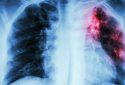

Типологията пациенти на заболели след зараза с коронавирус в Италия се мени. В сравнение с началото на епидемията сега все по-често 40-годишни влизат в интензивна терапия, каза в тв интервю за “Раи Нюз 24” лекарят Лука Лорини от болницата “Папа Йоан XXIII” в Бергамо. Градът е сред най-засегнатите от епидемията в Италия – само до 11 март броят на заразените в него е 1815 – първо място в област Ломбардия, пише „24 часа”